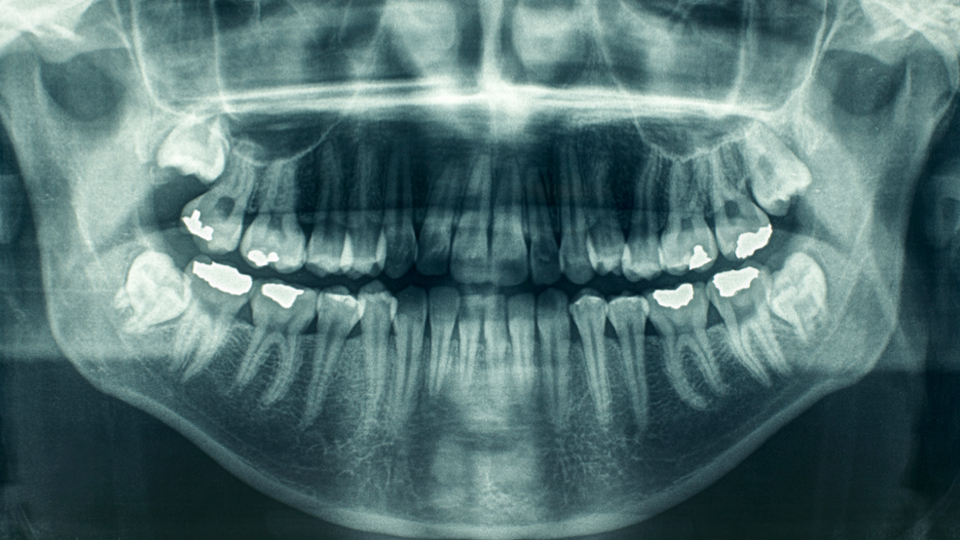

จัดระเบียบ ‘เครื่อง X-RAY ฟัน’ ทันตเเพทย์รุกต้าน ข้อเสียมากกว่าดี

เอกซเรย์ฟัน (ที่มา:http://www.vcharkarn.com)

เครื่องเอกซเรย์ทางทันตกรรม (ที่มา:http://www.armydent.com)